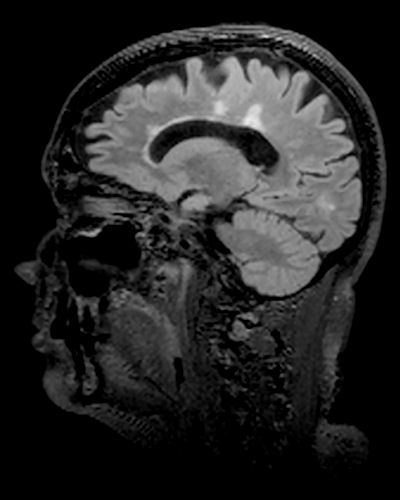

MS characteristic lesions

Mark the largest lesion